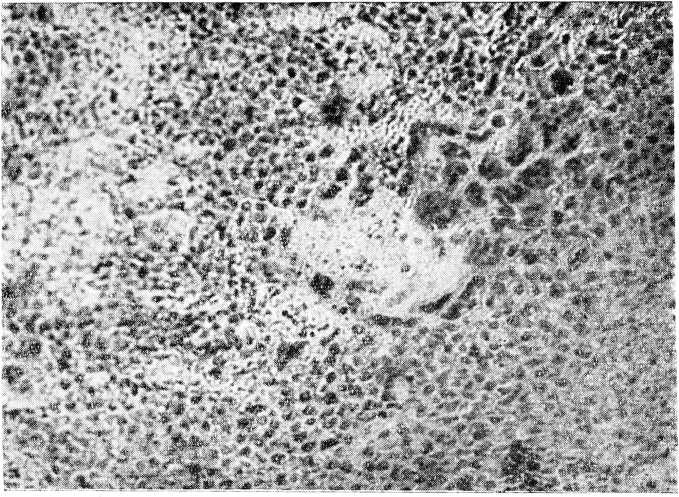

Переход положительной реакции сперматоурии в отрицательную свидетельствовал против наличия хорионэпителиомы, поэтому 12/VI гистологический препарат соскоба из полости матки консультирован проф. П. В. Маненковым: выраженная децидуальная ткань, сохранившиеся хориальные ворсины с отеком ткани, как при пузырном заносе. Местами вокруг ворсин разрастание хориального эпителия в виде полей, напоминающих ткань хорионэпителиомы, в других кусочках препарата эти поля клеток прилегают к некротическому слою; имеются островки слизистой тела матки с резко выраженными децидуальными изменениями и пиловидными железами. Диагноз: пузырный занос с необычно выраженным разрастанием хориона, похожим на хорионэпителиому (рис. 1).

Рис. 1